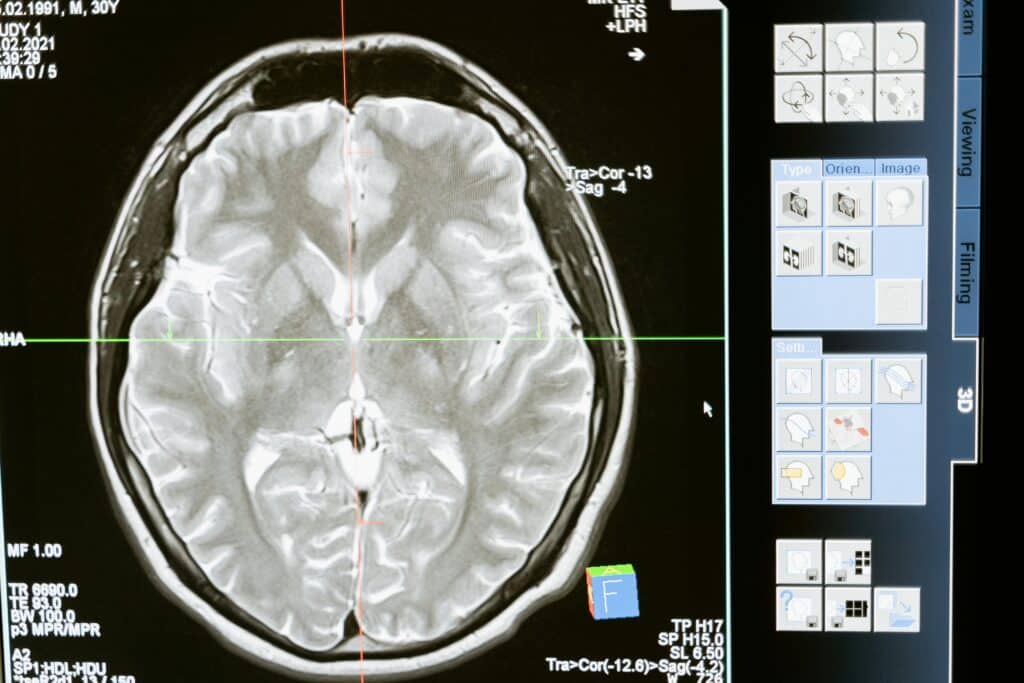

Diagnosis of Encephalitis

Timely and accurate diagnosis of encephalitis is essential for initiating treatment. Common diagnostic methods include:

- Physical and Neurological Exam: Checking reflexes, sensory function, and mental status to assess neurological impact.

- Imaging Tests: MRI or CT scans can help identify areas of inflammation or brain swelling.

- Lumbar Puncture: A spinal tap may be used to collect cerebrospinal fluid to detect signs of infection or inflammation.

- Blood and Urine Tests: These tests help identify infectious agents or abnormal immune responses.

- Electroencephalogram (EEG): Used to monitor brain activity, especially in cases where seizures are present.